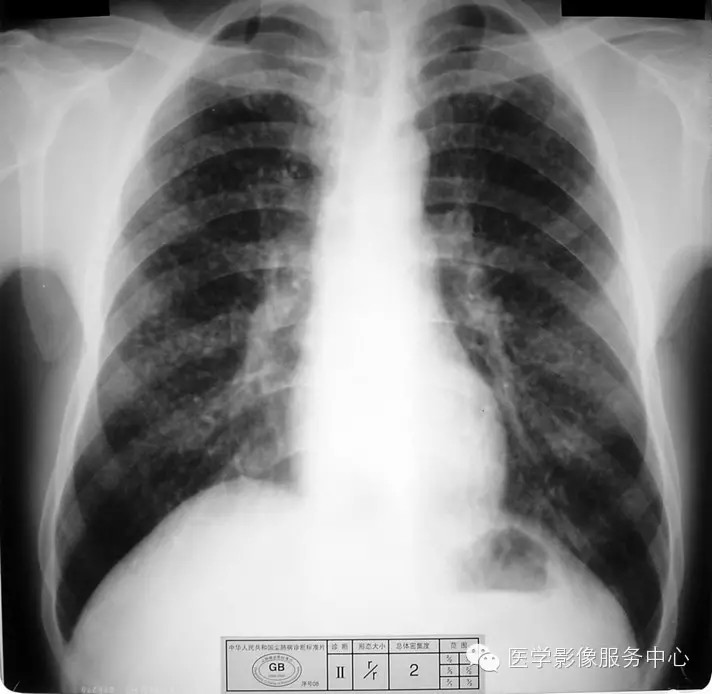

4.3 二期尘肺(Ⅱ)

a)Ⅱ:有总体密集度2级的小阴影,分布范围超过4个肺区;或有总体密集度3级的小阴影,分布范围达到四个肺区。